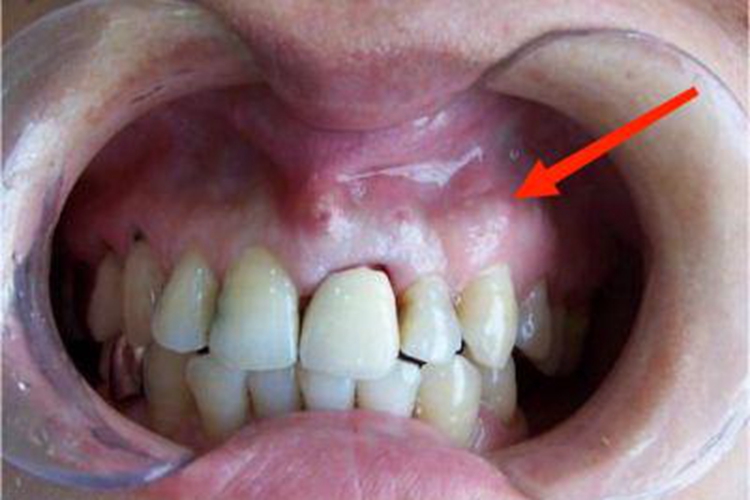

常因急性期过后未及时治疗或反复急性发作所致,可见牙龈表面有窦道开口,开口处可以平坦,需仔细检查才可见有针尖大的开口,也可呈肉芽组织增生的开口,压时有少许脓液流出,叩痛不明显,有时可有咬合不适感或钝痛。